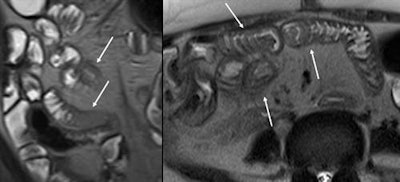

Coronal and axial T2-weighted HASTE images at cytomegalovirus enteritis in HIV positive patient showing mural thickening with T2 hyperintense appearance (arrows).

Coronal and axial T2-weighted HASTE images at cytomegalovirus enteritis in HIV positive patient showing mural thickening with T2 hyperintense appearance (arrows). Dr. Amir Reza Radmard.